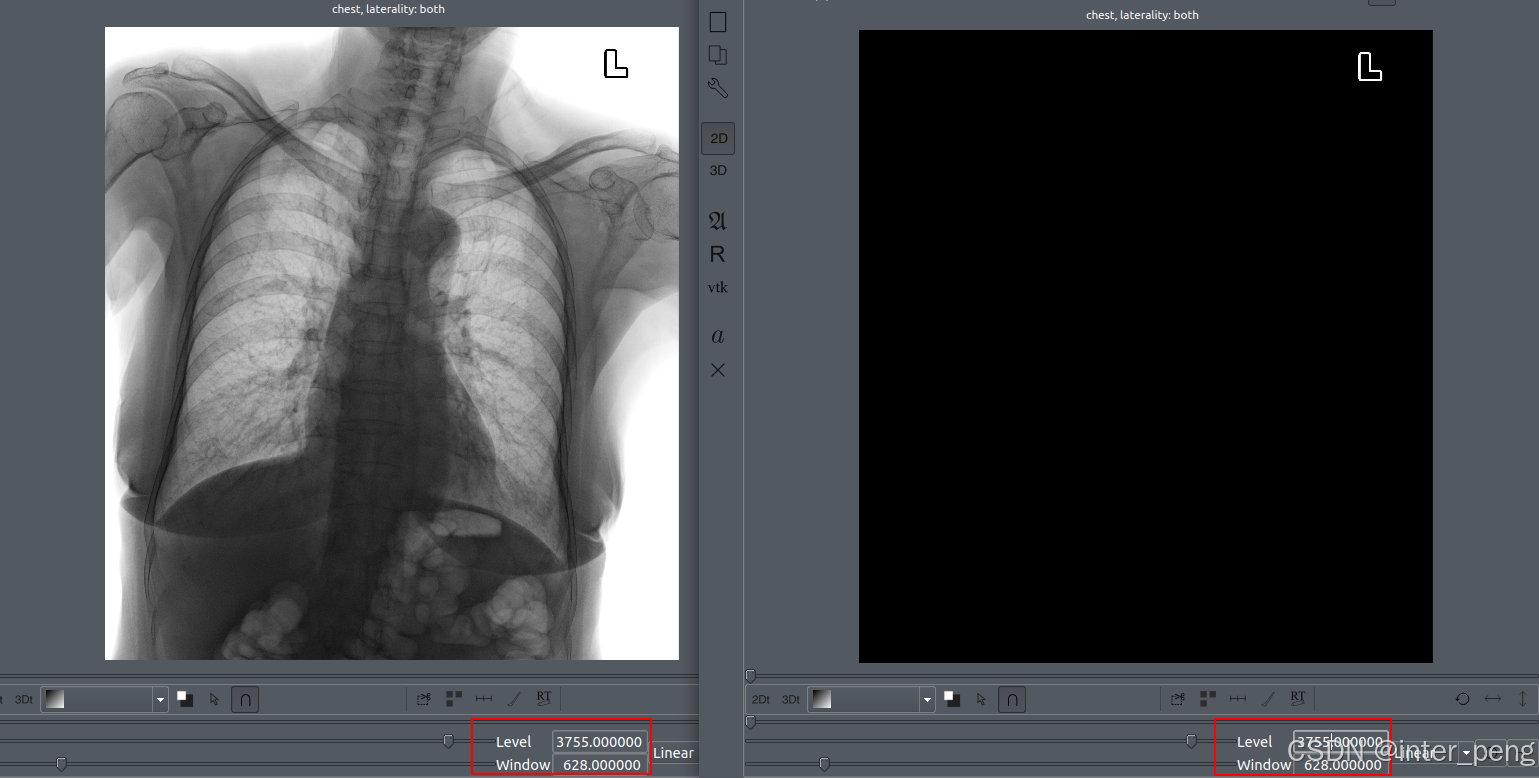

根据以上的函数, 输入一张反片的图像,经过处理后, 预期是应该得到正片图像. 但实际得到的, 用软件查看, 是一张黑图.

输入图像:

处理后的图像变成了:

看到这个结果, 第一反应有点懵. 不知道是什么原因.

查看了反色后的图像, 它的pixel_array, 也都是正常的. 原来的像素最高的像素点, 灰度值变成了最小值, 其他的像素点, 灰度值也都发生了翻转.

后来, 我也不知道是什么原因, 就索性调整了一下, dicom viewer软件下面的窗宽窗位的滑块.

这时, 随着窗位(WindowLevel)不断调整, 原来黑色的图像, 慢慢地就显示出了, 反色校正后的图像, 就像变魔术一样.

这个时候, 我才恍然大悟.

在进行反色校正后, 还有一步必须要做的工作, 就是需要将它的窗位也相应进行一个翻转.

以上是, 在同一个窗宽窗位下面, 左侧是反色图, 右侧是校正后的图的表现.

由于图像的拍摄后的窗宽窗位, 是为了原来的反片, 能够正常展示的.

那么, 在图像整体的灰度值都发生了翻转后, 如果还沿用原来的窗宽窗位, 肯定是没办法显示正常的.

最重要的是窗位WindowCenter, 它决定了整个窗宽的上限和下限, 也就决定了, 这个图像的灰度可见范围.

因为小于下限的灰度值, 都会是黑色;大于上限的灰度值, 都会是白色. 只有在窗宽范围内的图像, 才是可以看出灰阶变化的.

根据上面的示意图:

大概的原理就是:

1, 由于图像整个像素的灰度都发生了翻转. 比如原来的ROI(感兴趣区域)的灰度值, 正好和当前的WindowLevel/Center = 3755是一致的, 所以可以在反片中, 看到ROI区域;

2, 经过反片校正后, ROI区域的灰度值, 从原来的3755, 变成了4096 - 3755 = 340.

如果维持当前的窗宽窗位不变, 只能展现: 3441 ~ 4069这个灰度范围内的图像, 而ROI区域的灰度值是340, 小于这个下限, 所以小于3441的区域, 都会被置为黑色.

这就解释了, 为什么第一次反片校正后, 整个图像都是黑色的了.

3, 将WindowLevel/Center从原来的3755, 调整为4095 - 3755 = 340, 那么能够显示影像的灰度范围, 就变成了 26 ~ 654的灰度区域.

而ROI的灰度值为340, 正好落在了这个灰度范围内, 所以就可以看到了.